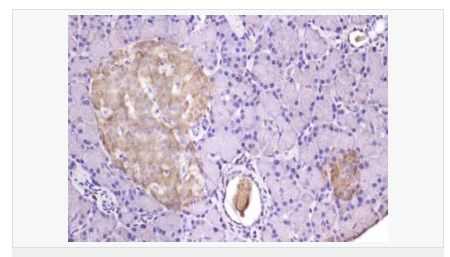

| 產(chǎn)品應用 | WB=1:500-2000 ELISA=1:5000-10000 IHC-P=1:100-500 IHC-F=1:100-500 IF=1:100-500 (石蠟切片需做抗原修復) not yet tested in other applications. optimal dilutions/concentrations should be determined by the end user. |

| 細胞定位 | 細胞漿 細胞膜 |